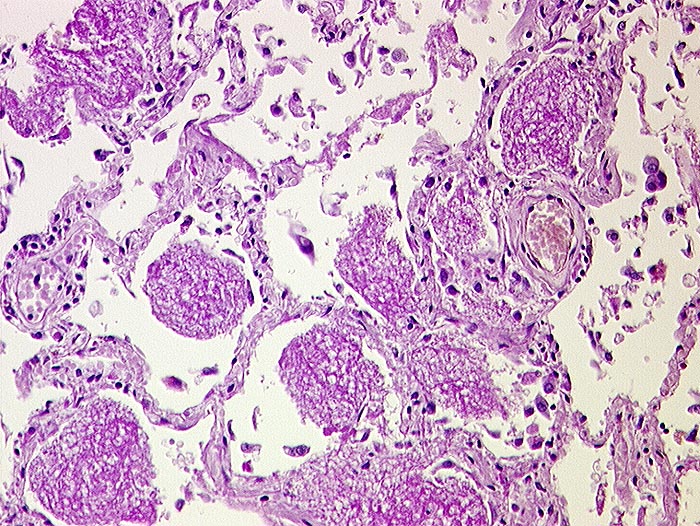

PathoPic – image database / PathoPic ID 550 - Pneumocystis jirovecii Pneumonie

Pneumocystis jirovecii Pneumonie

Wabiges, körnig schaumiges intraalveoläres PAS-positives erregerhaltiges Material. Wegen Immunsupression nur gering ausgeprägtes interstitielles entzündliches Infiltrat. In dieser Färbung sind keine Erreger erkennbar.

Immunsupressive Behandlung wegen Systemvaskulitis.